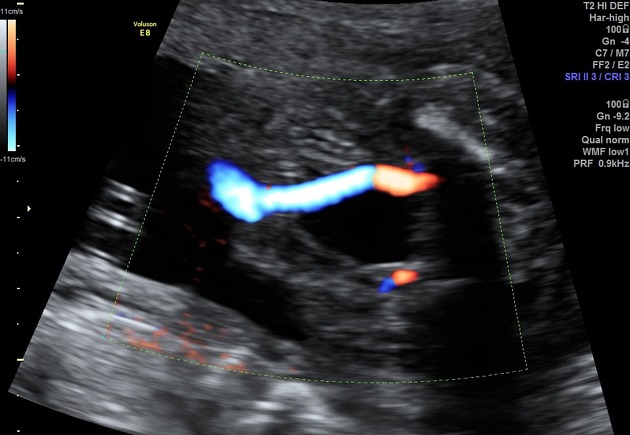

Có một bẫy hay gặp khi đánh giá số mạch dây rốn. Nếu chỉ quan sát đoạn dây rốn gần bánh nhau, hai động mạch có thể dính vào nhau trong một đoạn ngắn. Khi đó, hình ảnh dễ bị hiểu nhầm thành dây rốn hai mạch. Để tránh nhầm lẫn, cần kiểm tra mạch máu chạy hai bên bàng quang của thai. Nếu chỉ thấy mạch ở một bên, điều này ủng hộ chẩn đoán chỉ còn một động mạch rốn.

Ngoài ra, tư thế thai không thuận lợi hoặc dây rốn xoắn nhiều cũng có thể làm việc đếm mạch khó hơn. Trong những trường hợp này, việc rà soát mạch quanh bàng quang vẫn là cách đáng tin cậy nhất.